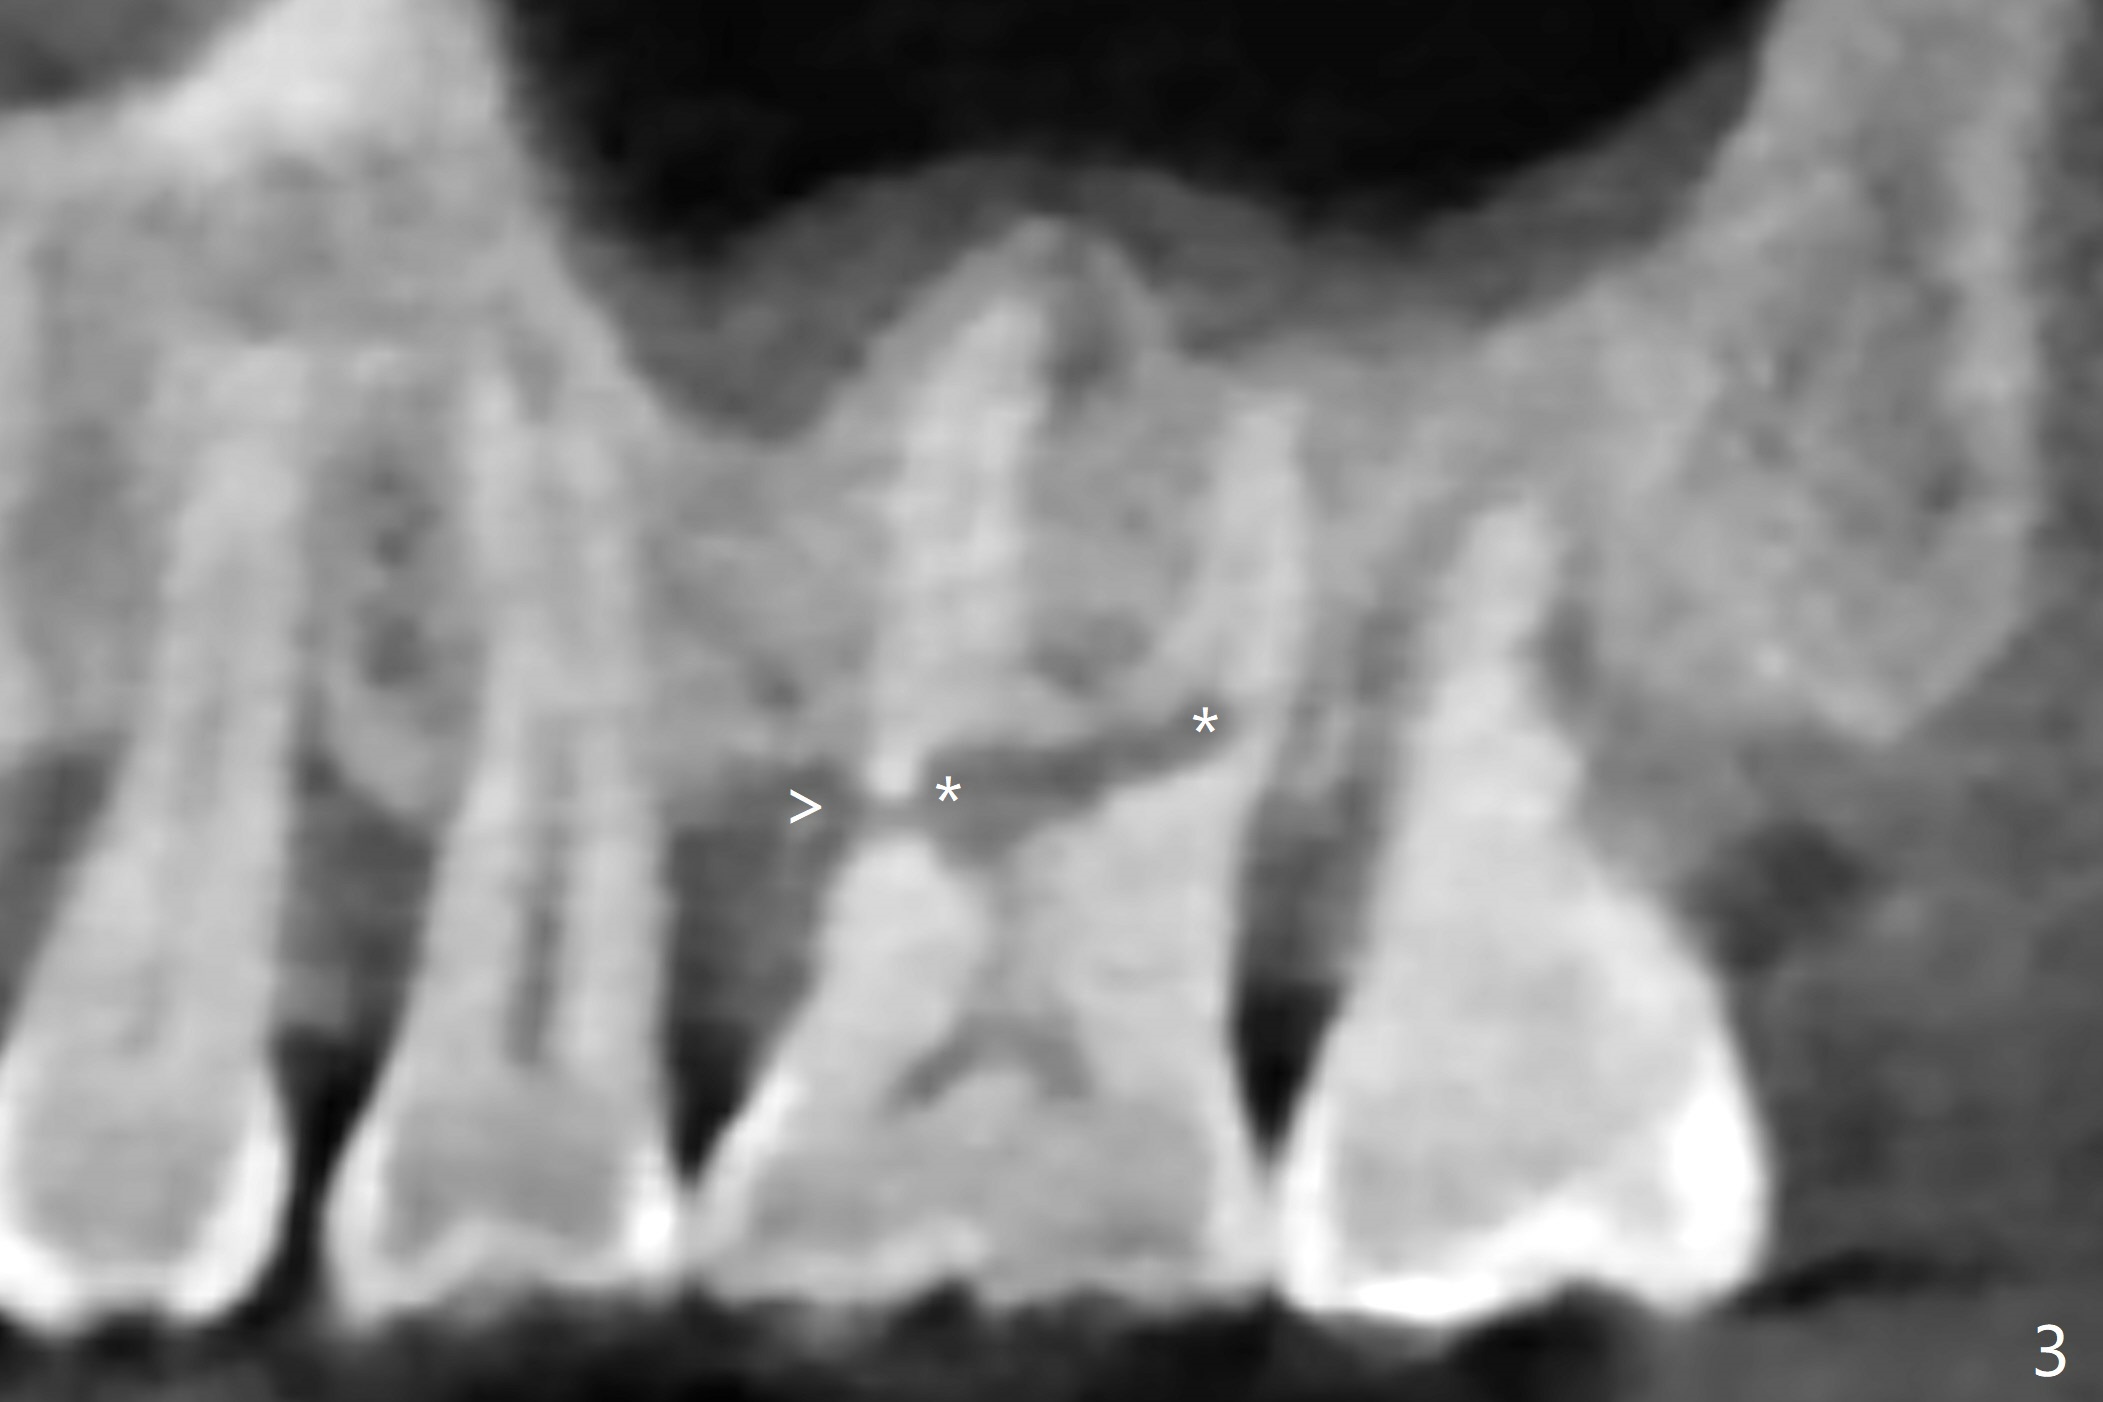

A 60-year-old man had buccal furca abscess at #14 with an unknown radiolucent lesion within the tooth five months earlier (Fig.1 *). Now the tooth is sensitive to cold. CBCT shows internal resorption involving the mesiobuccal and distobuccal roots (Fig.3,4 (axial section) *) with exits mesially (Fig.3 >) and buccally (Fig.2 ^). There is periapical radiolucency of MB (Fig.3,7) with the thickened overlying sinus membrane (Fig.3,5,6 (*), as compared to that over the tooth #3 (Fig.6)). Osteotomy will be established in the septum away from the lesion (Fig.8 red circle) and for 5 mm (Fig.5 (coronal section)). He is a heavy bruxer, loosening Ketac-cemented unipost. Use PRF to repair the defect associated with the MB lesion and sinus lift.